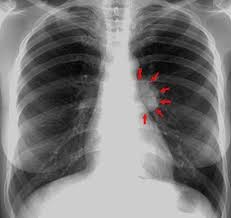

Paciente masculino de 23 años quien es llevado a consulta por productiva, malestar general fatiga y

disnea. Menciona además que últimamente ha tenido que utilizar más veces al día

su tratamiento de rescate para asma. Entre los antecedentes menciona que cree

que la Pachamama es perfecta, así que se come todas las verduras tal cual las

recoge de la siembra sin lavarla ni hervirla. Además, menciona tener malestar

abdominal, dolores tipo cólico, náuseas, meteorismo, vómitos ocasionales y

diarrea. Se le realiza un examen de heces que menciona que tiene

"huevos" y una biopsia pulmonar que verán a continuación... Con base

a toda la información... ¿Cuál de las siguientes radiografías torácicas es más

probable que tenga este paciente?

0%